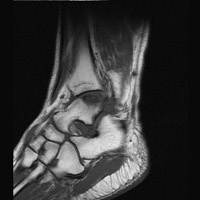

- Click on the image for a larger versionDSagittal MRI. This T1-weighted image shows a region of low signal intensity representing the site of osteochondritis dissecans and edema.